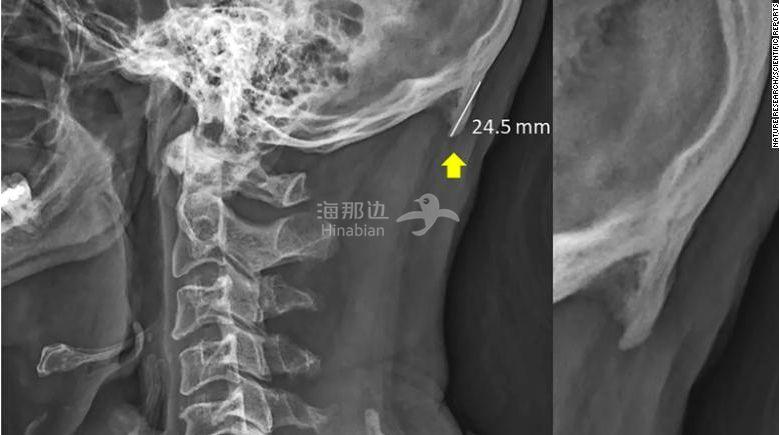

CNN在新闻中给出了一组数据对比图片:

年轻群体,男性枕外隆突情况比女性严重,30-50岁年龄层,女性比男性更严重,50岁以上,男女出现枕外隆突的情况相同。

平均数值大概在24.5mm左右。